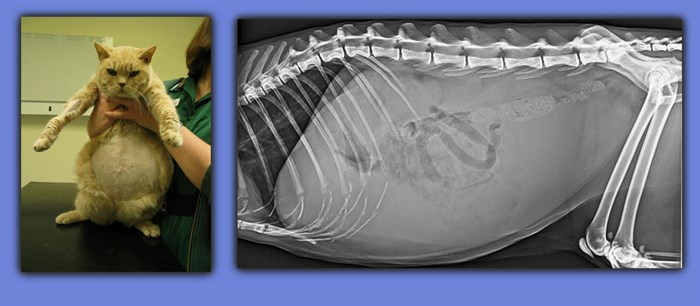

Истончение костей у кошек: причины и решения

Раздел: Мудрость в объективе